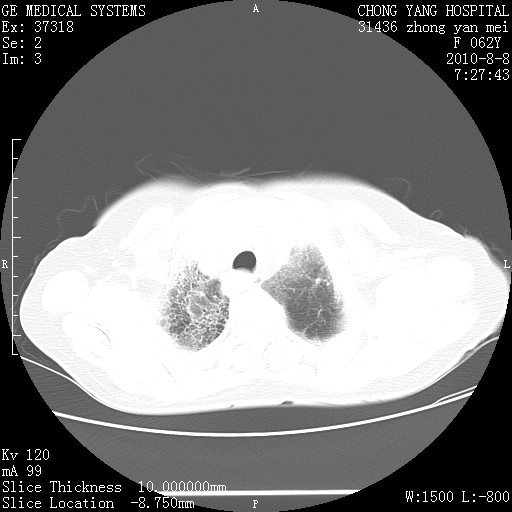

标题: CT28269:F62Y咳嗽胸痛数月。 [打印本页]

标题: CT28269:F62Y咳嗽胸痛数月。

两肺弥漫性间质纤维化伴继发性支扩。

考虑特发性肺间质纤维化

考虑两肺间质性肺炎并肺间质纤维化。

双肺间质纤维化合并感染、肺气肿

双肺间质纤维化

两肺间质纤维化并牵拉性细支气管扩张。

考虑两肺间质性肺炎并肺间质纤维化,肺气囊形成。